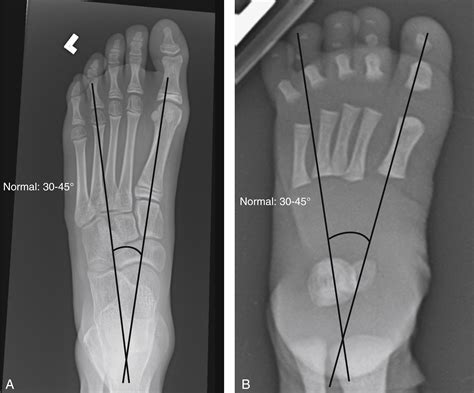

• X-rays: Often the first line of defense for bone fractures or lung issues.

X-ray Minimal Bone fractures, pneumonia, chest congestion